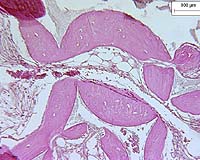

The experiments were done using mouse mammary and fibroblast cells. The researchers used three different processes for reprogramming the cells to a "stem," or embryonic, state. The first method was developed expressly for this study, and the others have already been well documented.